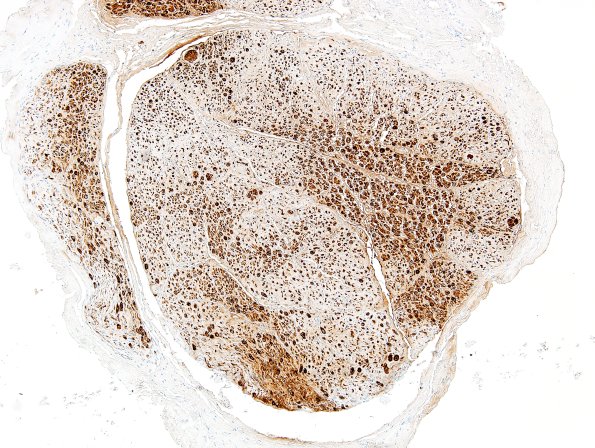

This portion of the sciatic nerve shows patchy loss of Schwann cells in this long term neuropathy. (S100 IHC)